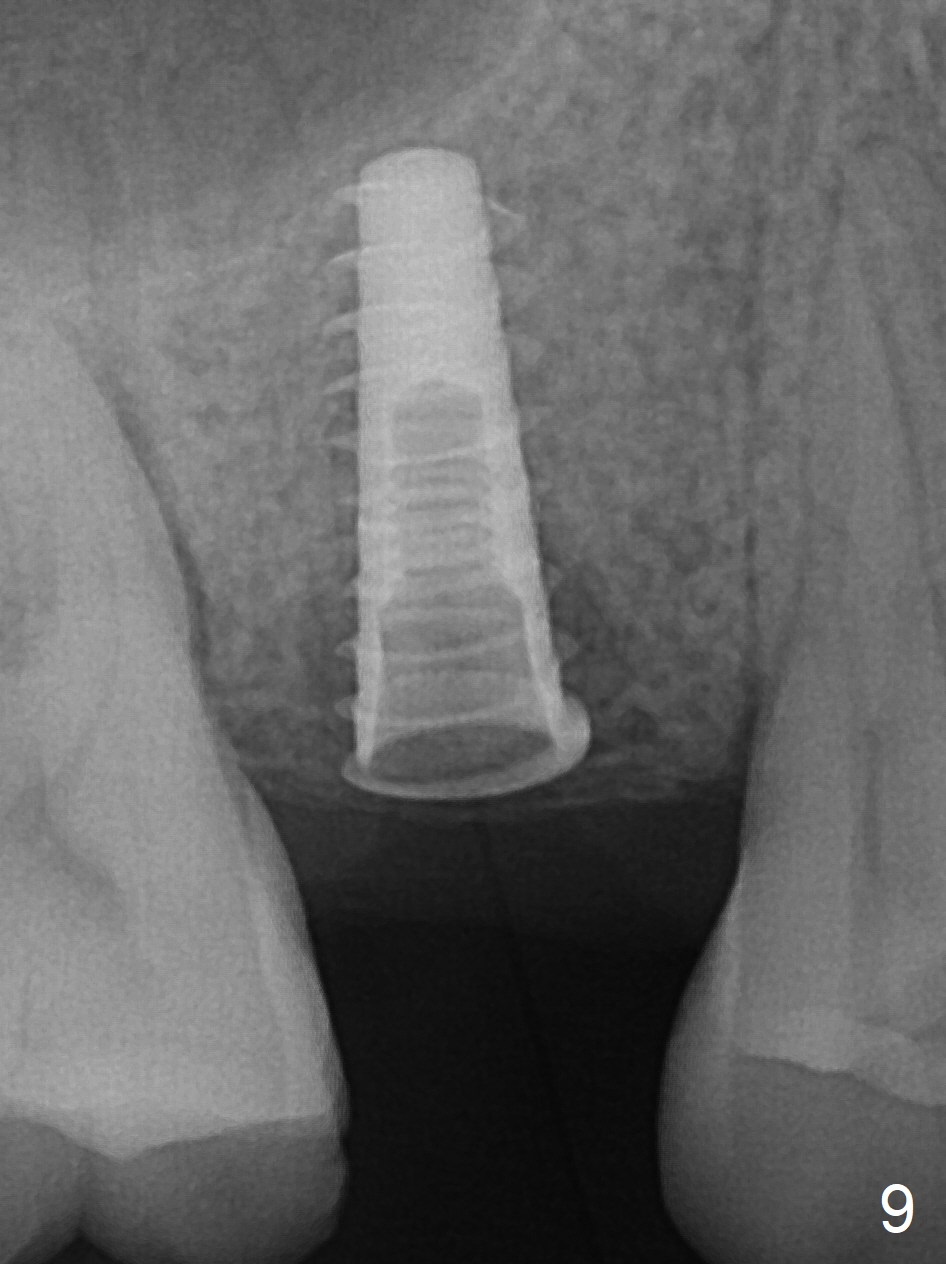

A 47-year-old man returns emergently with subgingival fracture of the lingual (L) cusp of the tooth #4 (Fig.1-3).  After extraction (no bony defect) without drilling, a 4x11 mm dummy implant is placed as a tap drill with satisfactory stability (Fig.4,5).  To get subcrestal placement, a shorter (4x9 mm) implant is inserted with insertion torque of < 35 Ncm.  In retrospect, a larger implant (4.5 mm) would be better in term of primary stability.  After allograft placement into the buccal and lingual gaps, a 4.5x4(4) mm abutment is placed for an immediate provisional.  There is a peri-implant gap 7 months postop (Fig.7<, as compared to the implant at #2 (6 months postop)) .  When the loose abutment is being retightened, the patient feels pain, although the gingiva appears healthy (Fig.8).  A larger implant should have been used; the abutment should have been removed.  The implant dislodges while the abutment is untightened 8 months postop.  The osteotomy is found intact.  A 4.5x11 mm dummy implant is placed 2 mm subgingival with 20 Ncm (Fig.9).  When a 4.5x11 mm definitive implant is placed 3 mm subgingival (Fig.10,11), torque reaches 50 Ncm.  A 5.5x3 mm healing abutment is placed.  Three months postop, the implant is stable (Fig.12,13) and impression is taken.